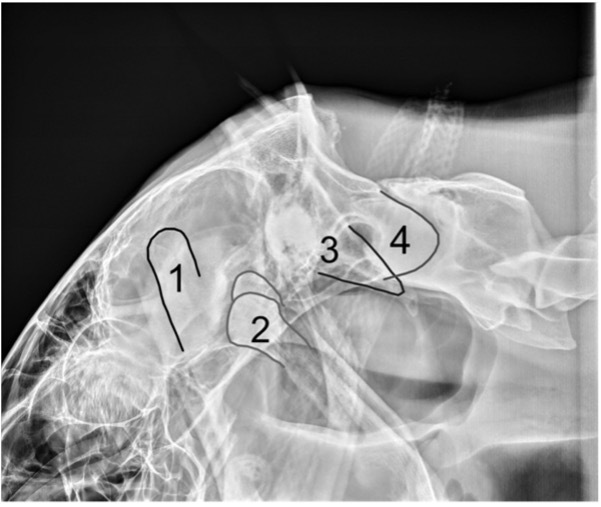

1 - coronoid process

2 - condylar process of mandible

3 - paracondylar process

4 - occipital condyle